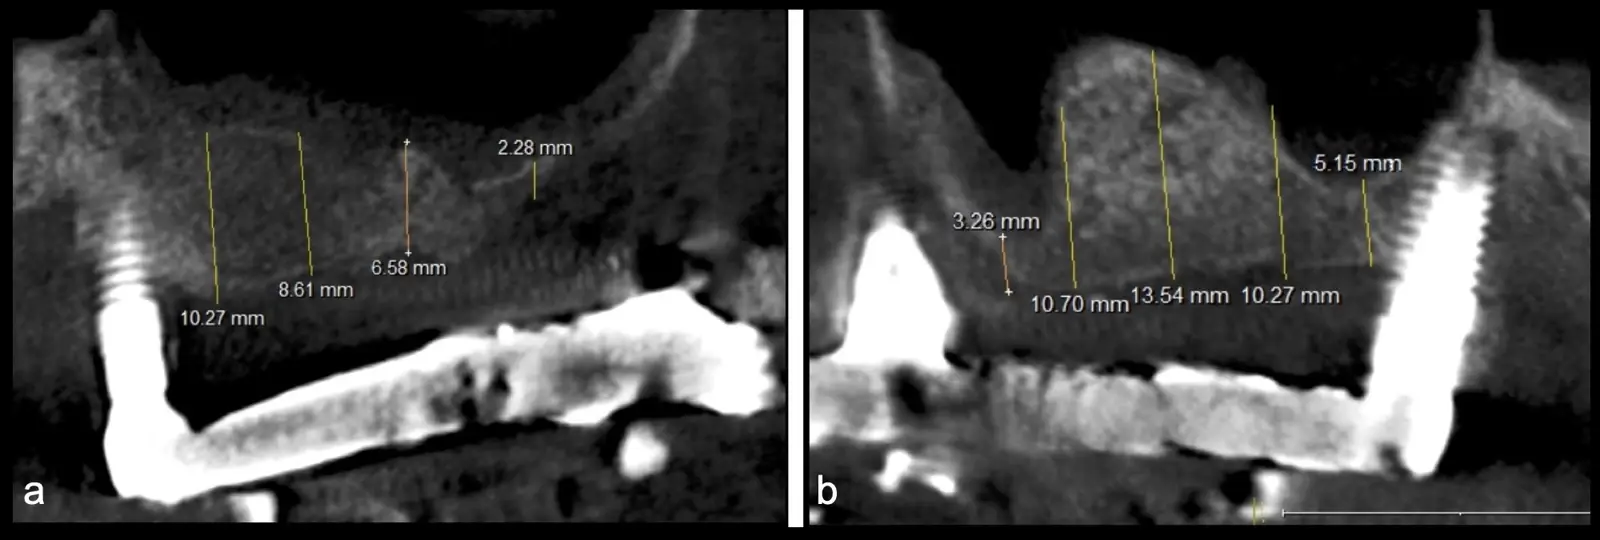

Figura 2. Espesor de la pared lateral (X), altura del reborde residual (Y), profundidad del seno maxilar (Z) y espesor de la membrana sinusal.

El tipo de inserto a ser utilizado dependerá del espesor de la pared ósea. Si la pared es menor a 0.5 mm, es mejor utilizar insertos de desgaste para prevenir la ruptura de la membrana de Schneider; si el espesor es mayor a 0.5 mm, se puede utilizar insertos de corte de espesor medio (Figura 3).

Paciente de 62 años, de sexo masculino, llega a la consulta para la colocación de implantes dentales. Refiere haber tenido tratamiento previo con implantes dentales, algunos de los cuales fueron perdidos. A la evaluación clínica se observa ausencia de piezas dentarias en el maxilar superior y 3 implantes remanentes. En la evaluación tomográfica se observa neumatización de los senos maxilares del lado derecho e izquierdo (Figura 14), para lo cual se indica el procedimiento quirúrgico de levantamiento de piso de seno maxilar en ambos cuadrantes, como paso previo a una nueva planificación implantosoportada.

Figura 14. Evaluación intraoral en donde se evidencia presencia de una prótesis híbrida soportada sobre implantes dentales, al retiro de la estructura se observó tornillo protésico fracturado (a, b, c). Evaluación tomográfica: corte sagital a nivel de los senos maxilares derecho e izquierdo, donde se observa una atrofia severa de los rebordes óseos acompañados de neumatización de los senos maxilar (d, f, g).